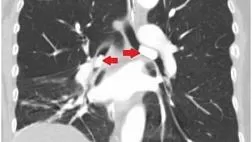

Пациентка обратилась с жалобами на прогрессирующую одышку и кашель в течение месяца. Рентгенография органов грудной клетки показала изменения в правом легком с небольшим количеством жидкости в правой плевральной полости. Но при компьютерной томографии грудной клетки инфильтрации или других изменений легочной ткани не обнаружено. Пациентке назначена эмпирическая антибактериальная терапия. При исследовании мокроты выявлен рост непатогенной флоры. Состояние пациентки продолжало ухудшаться, что потребовало интубации трахеи и искусственной вентиляции легких. При повторной КТ грудной клетки выявлены гиперденсные образования в просвете левого главного (размер 2,2 см) и промежуточного бронхов (размер 1,5 см), обтурирующие их (рис. 1, 2).

Рисунок 1 [1].